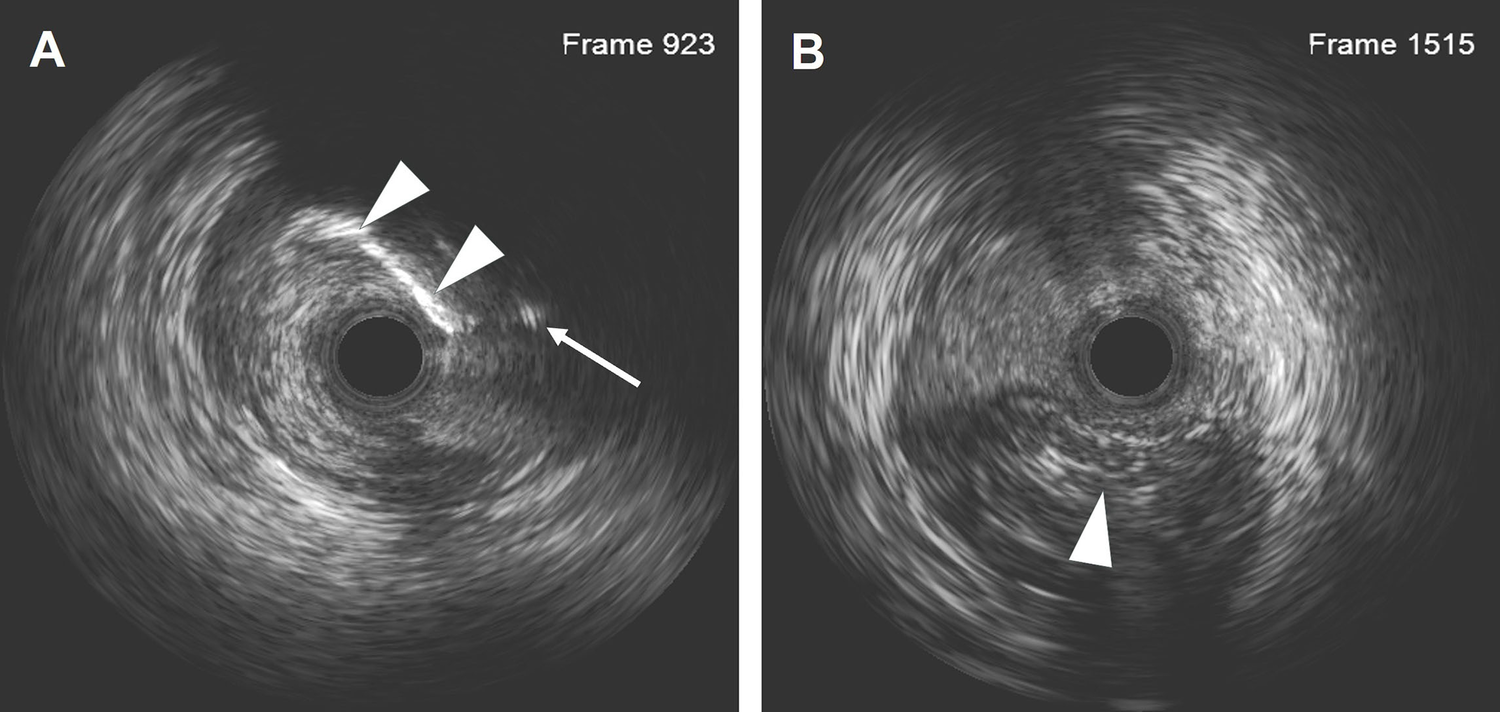

Figure 3

IVUS results after the LAD recanalization retracking sequences from the D1 vessel to the LAD and from the LAD distal true lumen. (A) The IVUS results showed that the retrograde wire entered the LAD vessel architecture through a calcification ring on the outer edge. The white arrow indicates the retrograde wire, and the white arrowhead indicates the calcification ring. (B) The IVUS results revealed that the wire was located in the subintimal space with a length of 18.2 mm. The arrowhead indicates the true lumen.

Dual angiography was performed and showed a proximal LAD CTO with a small stump, with ∼30 mm extending from the proximal to mid-LAD and several septal collaterals from the right coronary artery (RCA), and a good landing zone distal to the mid-LAD. Furthermore, it showed that the first large diagonal (D1) vessel was occluded within the LAD CTO lesion, and that two-thirds of its distal length was retrogradely filled via ipsilateral vessels, making it visualize as a larger vessel (Figure 1B, Supplementary Videos 1, 2). The primary antegrade approach was attempted with a Pilot 200 wire, which was successfully navigated into the distal true lumen of the D1 vessel (Figure 1C, Supplementary Video 3). After a 2.0 mm × 20 mm semi-compliant balloon dilation in the D1 vessel segment, dual CAG revealed that the LAD occlusion entry point was ambiguous. With the support of a dual lumen catheter (DLC), Gaia3 and Pilot 200 wires were used to explore the occlusion entrance, gaining access to the subintimal space. Subsequently, a knuckled Pilot 200 wire was tracked forward with a Corsair catheter, which appeared to be directed toward the septum rather than into the LAD course (Figure 1D, Supplementary Video 4), and intravascular ultrasound (IVUS) revealed that the entry point was incorrect. Next, several retrograde attempts were performed with softer wires such as SION/SION and Black/SUOH03 across the septal vessels, respectively, but these all failed. The following antegrade angiography revealed an Ellis type Ⅲ perforation (Figure 1E, Supplementary Video 5) located at the mid-LAD segment, which was likely caused by the knuckled Pilot 200 wire with the Corsair microcatheter tracking outside of the LAD architecture. Promptly, a 2.5 mm × 20 mm compliant balloon was used to tamponade from the D1 vessel to the proximal LAD and effectively controlled the pericardial bleeding (Figure 1F). In this situation, the retrograde approach was initiated again. The tip of the Sion wire, with a double-angled shape, crossed the RCA epicardial collateral vessel, which was connected to the septal vessels, as visualized by tip injection (Figure 2A, Supplementary Video 6). Stiffer wires, such as Pilot200/Gaia3, failed to penetrate the fibrous cap of the LAD CTO where it intersected with the D1 branch. Next, a knuckled Fielder XT-A wire was pushed forward into the LAD CTO body. Although reverse-controlled antegrade and retrograde tracking (r-CART) was performed, the UB3/Gaia3/CP12 stiffer wires all failed in the antegrade extension catheter (Figure 2B). Then, an antegrade parallel wire, with DLC support, was advanced as close as possible toward the retrograde wire (Figure 2C), and the extension catheter was subsequently delivered across the bifurcation, and successfully picked up the retrograde wire (Figure 2D). IVUS results, retracing from the D1 vessel to the LAD, confirmed that the retrograde wire entered the LAD vessel architecture through the outer edge of the calcification ring in the mid-LAD segment (Figure 3A), and from the LAD distal true lumen showed that the subintimal length was 18.2 mm (Figure 3B). To ensure adequate adhesion of the dissection flaps onto the perforation, multi-size balloon dilation for the D1 branch and the LAD, and 3.0 mm × 38 mm/3.5 mm × 38 mm DESs were deployed sequentially from the distal to the proximal LAD. IVUS was used to assess the optimal stent expansion and apposition. CAG showed that the perforation was completely sealed and there was thrombolysis in myocardial infarction (TIMI) grade III flow in the entire LAD (Figure 2E). Furthermore, the ostium of the D1 vessel was crushed, but good retrograde filling from the ipsilateral vessels was still observed (Figure 2F).